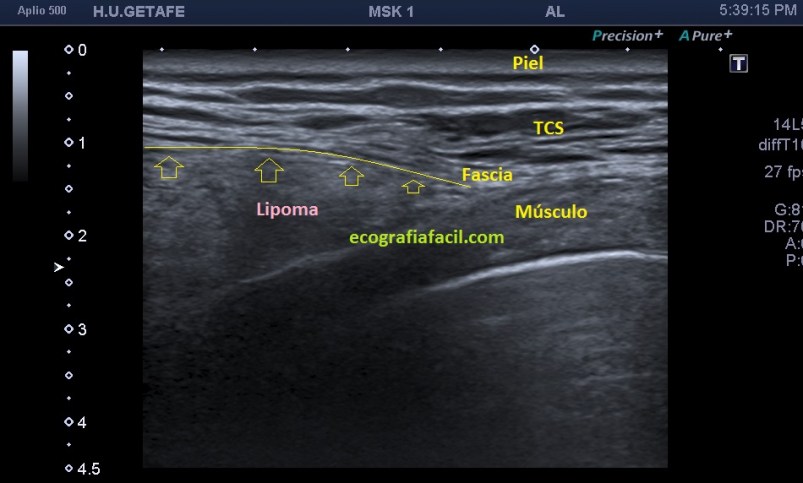

La imagen marca la línea amarilla que es la fascia de separación entre el músculo y el tejido celular subcutáneo que me vale para enlazar con otro gran aspecto a tener en cuenta en el estudio de los lipomas, que es su situación. Cuando tenemos un lipoma es super importante saber si es subcutáneo o es intramuscular por que el manejo terapéutico y para eso quiero que te fijes en la imagen superior, si miras la línea amarilla, está marcando la separación entre TCS y Musculatura.

Si el lipoma está en el tejido celular subcutáneo estará por encima de esta línea amarilla, si es intramuscular, estará por debajo, de este modo debemos reconocer siempre las distintas semiologías del tejido superficial y estar muy pendientes de las fascias entre el tejido celular subcutáneo y el muscular, fácil de discernir, por otro lado en la mayoría de las ocasiones.